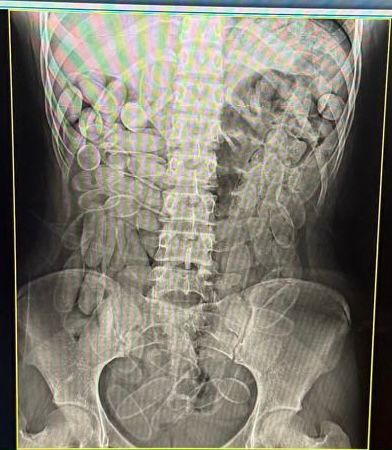

Investigação começou após apreensão de cápsulas de cocaína organismo de 15 pessoas – Foto: Divulgação

Diante da situação, ambas foram encaminhadas à Santa Casa de Corumbá, onde um exame de raio-x constatou que havia várias cápsulas do entorpecente no organismo. Elas confessaram terem engolido, cada uma, 102 cápsulas, para fazer o trabalho de “mula”.

No dia 14 de janeiro, bolivianas foram presos com 102 cápsulas de cocaína no estômago (Foto: Divulgação / Receita Federal)